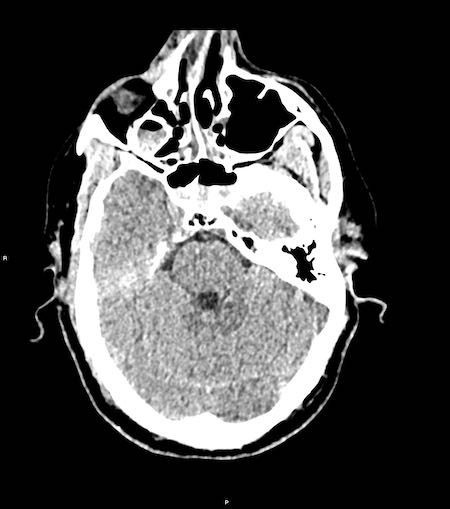

Bệnh nhân nam 46 tuổi bị chấn thương năng lượng cao khi đi xe máy.

Điểm EMV ban đầu là 2-5-3 và đồng tử hai bên giãn không phản xạ ánh sáng.

Hình ảnh CT

- Xuất huyết dạng chấm ở cả hai thùy trán.

- Gãy xương Le Fort II hai bên.